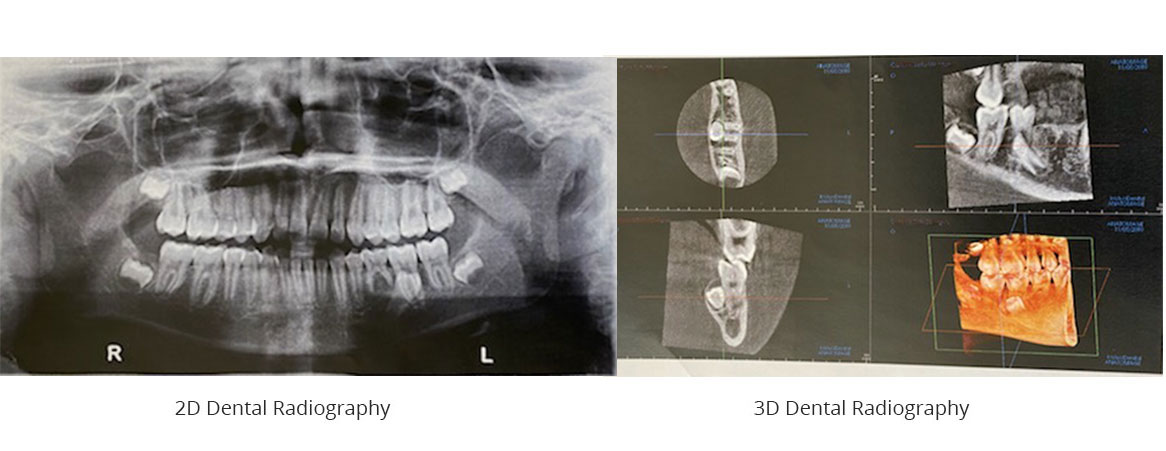

The amount of information collected by these X-rays is significant. Dr. David can see:

• your jaw bones;

• your full dentition;

• overlapping teeth;

• pathologies that are not always visible in 2D;

• the location of your nerves;

• the density of your bone mass in preparation for dental implant surgery.

For these and other reasons,

3D dental radiography is very effective in planning implant surgery, extractions, bone grafting and other precision surgeries.